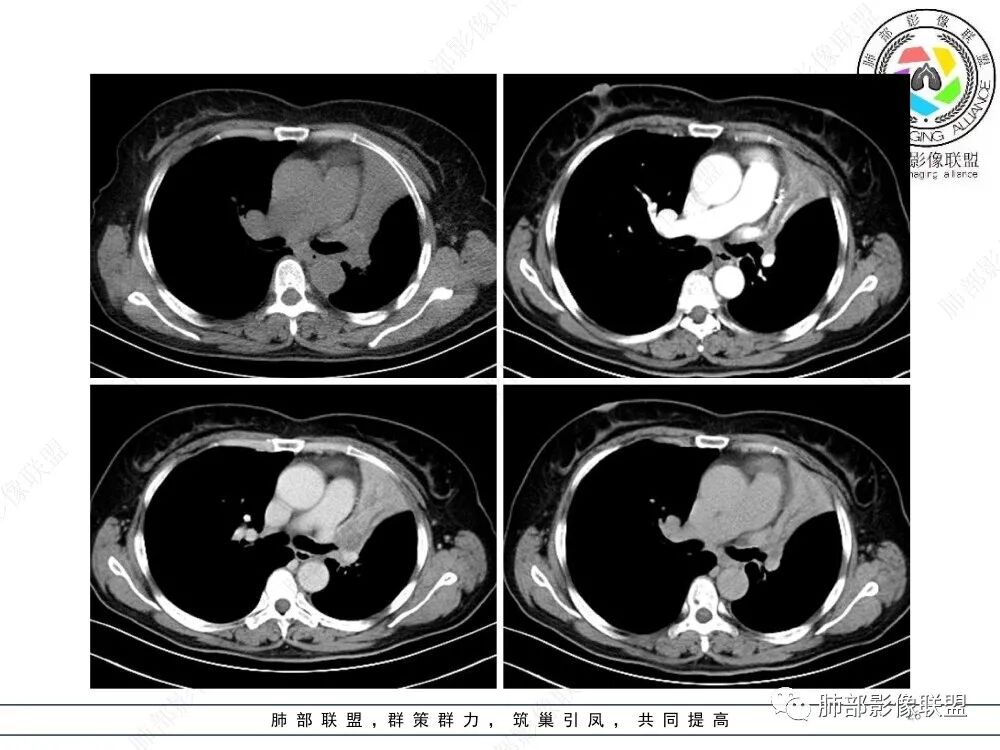

2、影像表现:正常肺背景,左肺上叶支气管腔内占位,上叶支气管截断,远端肺组织不张,强化差异衬托出肺门区结节影或块状影。增强扫描腔内占位轻中度不均匀强化,可见坏死,远端粘液栓,局部肺动脉受压、侵犯,纵膈淋巴结无明显肿大,无胸腔积液。

病灶腔内位主,局部膨隆凸向上叶支气管,两侧壁不清,病灶明显突出于壁外。

外形近端膨隆,远端收缩。

局部肺动脉受压明显,受压处似乎有点边界不清。

远端走形自然,提示远端不张,强化最明显处应该是单纯不张肺组织。

近端病灶内强化偏低,提示有侵犯。

综上,腔内占位明确,周围侵犯明确,支持支气管腔内恶性肿瘤,并阻塞性不张。